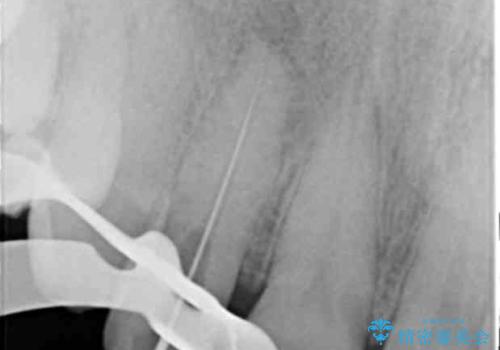

- 前歯の付近、歯ぐきを押すと違和感を感じその改善を求めて来院されました。

X線検査の結果、失活(感染根管)であることが判明したので、感染根管治療後セラミック補綴を計画します。